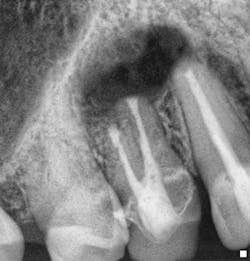

Fig. 4: Endodontic surgery performed without adhering to contemporary microsurgical principles. An apical seal is not evident and apical pathology has developed radiographically with associated swelling and symptoms.

Fig. 5: Microsurgical endodontics performed to correct the deficiencies in existing surgical treatment that took place less than six months ago. Apical repreparation performed using ultrasonics and MTA to create an ideal apical seal. A bone graft and resorbable membrane were used to maximize osseous and soft tissue healing. Microsurgical endodontics should be presented with confidence to patients as a potential treatment option for the management of clinical cases where there are ...